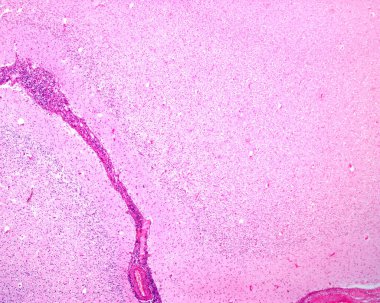

İnsan motor korteksi, fotomikrograf kortikal katmanlarda piramit nöronları gösteriyor gönüllü hareket kontrolü ve motor koordinasyonundan sorumlu..